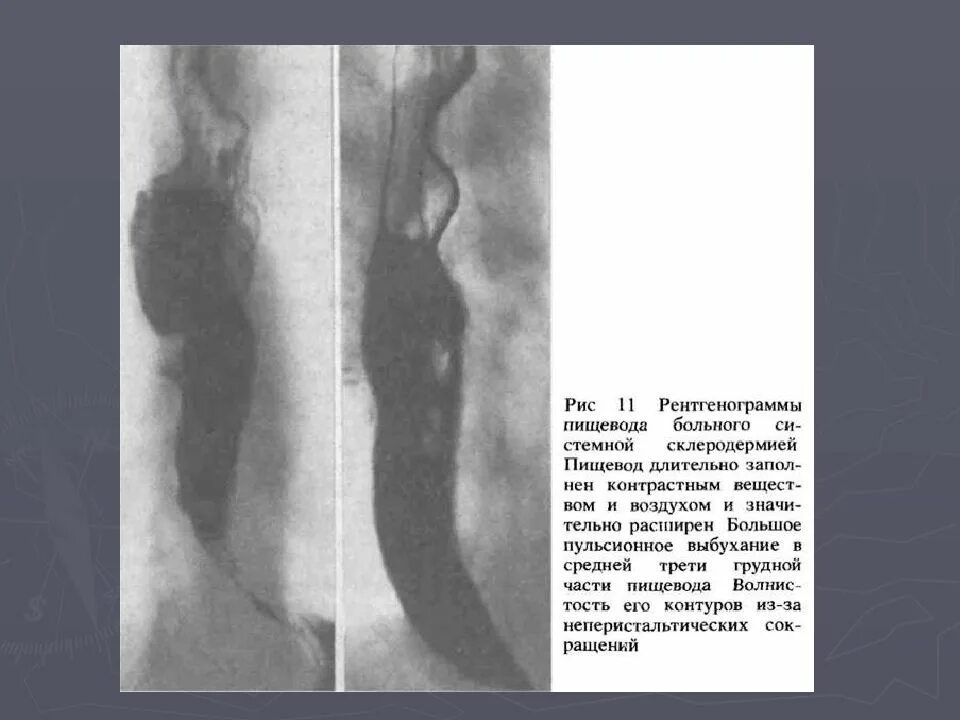

Стеноз пищевода симптомы